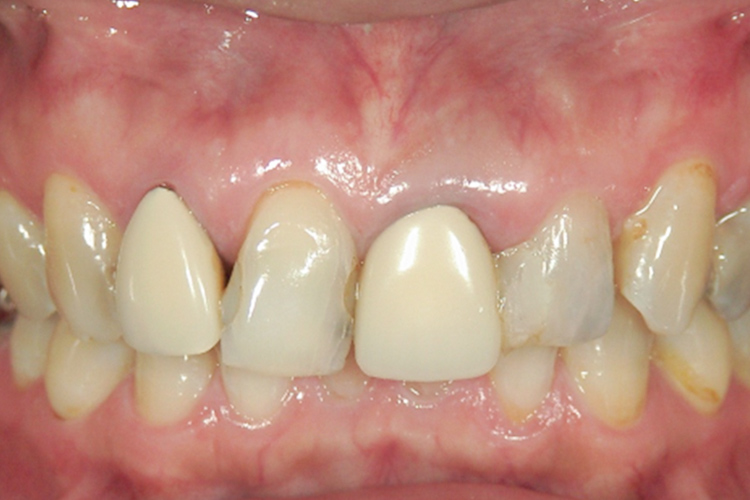

治療前

治療後